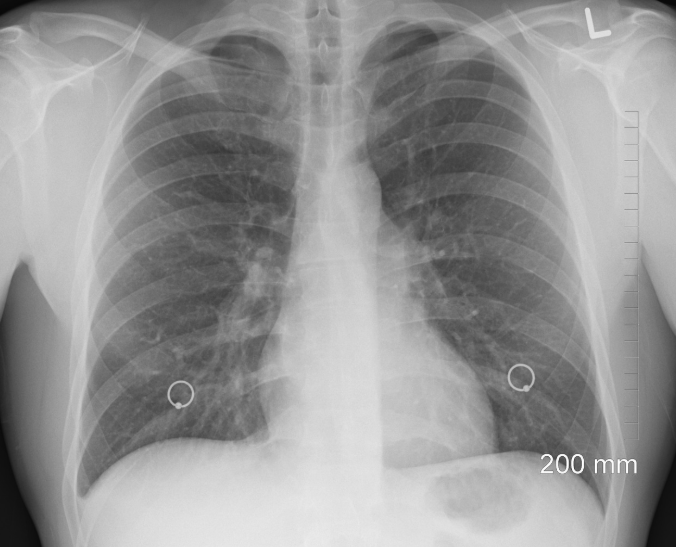

정기 건강검진: 특히 40세 이상, 흡연자, 대기 오염 노출이 잦은 직종 종사자는 폐 CT나 흉부 X-ray 검사를 권장합니다.

저선량 CT(LDCT) 검사: 고위험군에서 조기 폐암 발견에 효과적입니다.